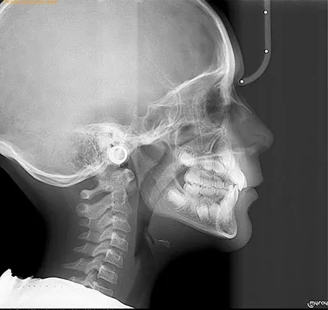

Facial growth assessment and monitoring are crucial in ensuring normal development and addressing potential issues as early as possible. Just like how pediatricians track overall growth, monitoring milestones in facial growth is equally important, particularly during the first two years of life.

While change might slow down as time progresses, it continues rapidly throughout adolescence. Dr. Wilkerson will closely follow facial growth and development as it impacts various aspects such as facial symmetry, aesthetics, a full smile, normal bite, TMJ function, optimal airway mechanics, and overall oral health.

By age 8, facial development is around 60% complete, and by age 12, it reaches approximately 90% completion. This makes childhood and adolescence the prime period for orthodontic treatments, as the growth rate and the ability of the facial structures to change are at their peak. Identifying and addressing problems or potential issues during this stage can significantly ease and expedite patient treatment.

It is recommended by the American Orthodontic Association that children should be evaluated by age 7. This makes early childhood the prime period for monitoring proper facial growth and development, as rapid growth of the face and jaws occur during this time period.

Problems that alter normal facial and jaw growth need to be identified early and treated so your child will have a great smile and a more beautiful face when they are older. By the time traditional braces are placed when permanent teeth are in, the face has limited growth into adulthood, leaving fewer options for treatment when there is more severe crowding, often leading to loss of pristine permanent teeth to make room or prolonged treatment times.